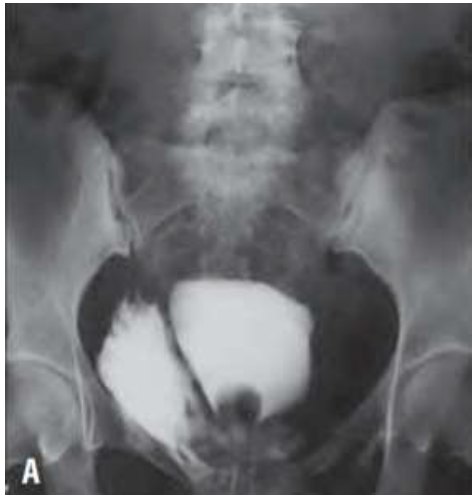

Mariana, 45 anos, é trazida pelo SAMU, vítima de acidente carro-moto. Suspeita de fratura de bacia. Refere dor abdominal intensa. Na admissão, realizado analgesia, coletados exames laboratoriais, avaliação da equipe da Ortopedia e realizado sondagem vesical para controle do débito urinário, com hematúria franca. Na hipótese de trauma de bexiga, foi solicitada pelo médico plantonista, uma cistografia retrógrada (imagem abaixo):